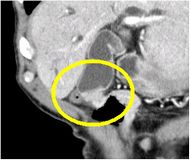

造影CT横断像(胆嚢がん)

造影CT冠状断像(胆嚢がん)